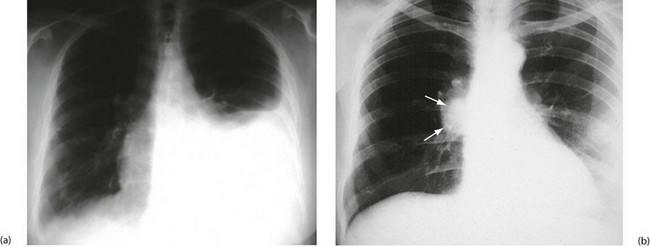

Stage IV (metastatic cancer) typically presents in younger women with poorly differentiated tumours that have spread to viscera. Recurrent pleural effusions result from pulmonary metastases (Fig. 45.16) and are managed with aspiration or pleurodesis (obliterating the pleural cavity by instilling tetracycline or bleomycin) or performing surgical pleurectomy. Ascites occurs secondary to liver involvement, and patients can present with nausea, anorexia, weight loss and jaundice. Lymphangitis carcinomatosa (widespread dissemination in skin or lung lymphatics) and fulminant liver metastases may occur in the terminal stage of the disease. Brain metastases can present with headaches and neurological symptoms due to a rise in intracranial pressure.